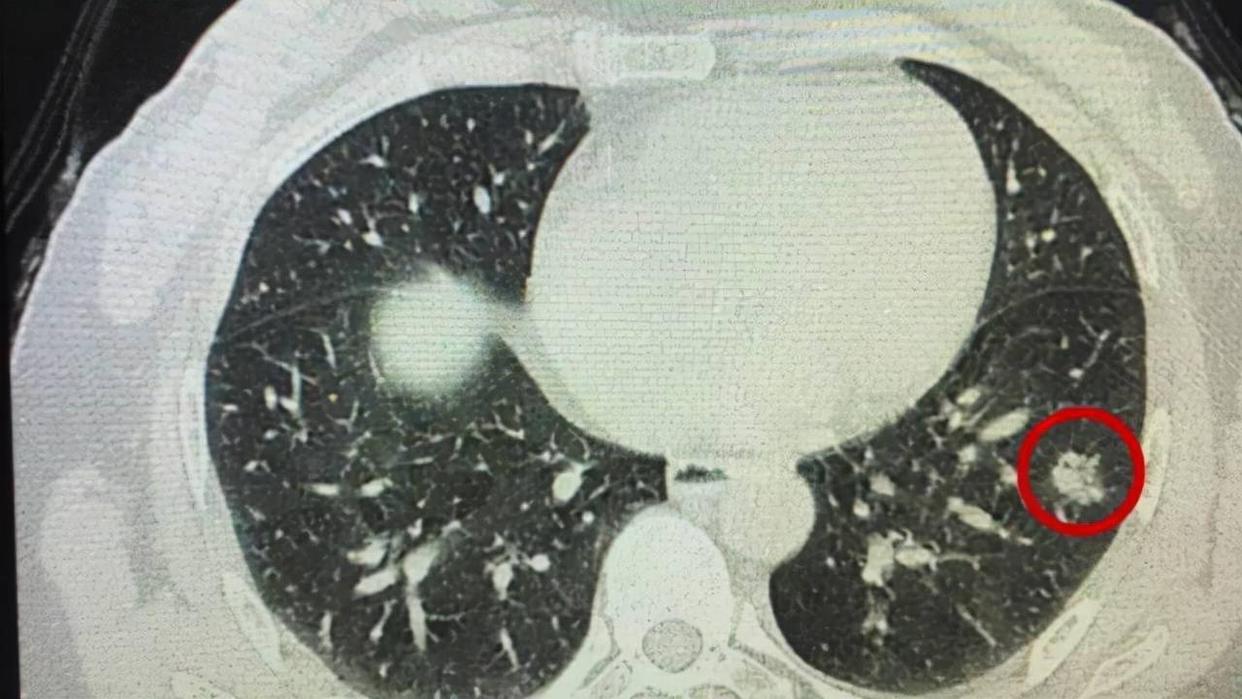

肺结节是一种影像学诊断,指的是肺内出现直径小于3cm的类圆形或不规则形的病灶,在胸部x线和胸部CT上多表现为胸部区域的密度增高,影也可单发也可多发。

根据病灶直径的大小,结节直径一般是在2~3厘米,直径小结节直径是小于等于两厘米微小结节直径小于等于一厘米,而肺结节并不特指于一种疾病,很多疾病也会导致肺部出现结节的问题,从而就会对身体造成伤害。

结节形态: 良性肺结节形态是规则的并且边缘清晰,而恶性肺结节一般形态不规则,边缘模糊。

结节大小: 肺结节小于0.8厘米,更大可能性是良性大于三厘米,更加倾向于恶性。

周围组织受累情况: 肺结节周围淋巴受到牵连,此时肺结节可能会出现恶化的情况。

结节密度: 良性肺结节密度一般都是比较均匀的,并且中心部分存在脂肪密度或者是空气,而恶性结节当中的密度是不均匀的,有时候会存在囊肿或者是坏死的症状。